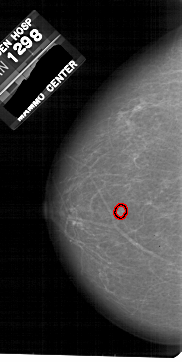

A_1812_1.LEFT_CC

LEFT_CC LINES 5416 PIXELS_PER_LINE 2716 BITS_PER_PIXEL 12 RESOLUTION 43.5 OVERLAY

FILE: A_1812_1.LEFT_CC.OVERLAY

TOTAL_ABNORMALITIES 1

ABNORMALITY 1

LESION_TYPE MASS SHAPE LOBULATED MARGINS MICROLOBULATED

ASSESSMENT 4

SUBTLETY 3

PATHOLOGY BENIGN

TOTAL_OUTLINES 1